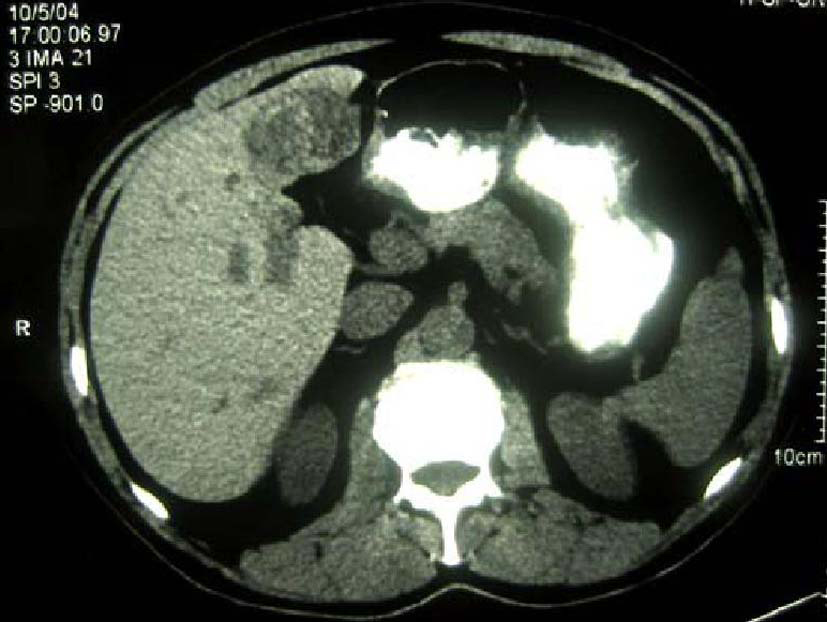

The patient was a 68-year-old Hispanic man who had a medical history of hepatitis B treated with lamivudin monotherapy, which was terminated in 2001. Periodic hepatic ultrasound follow-up showed a mass on the left lobe of the liver. A CT scan of the abdomen revealed a 4.0 cm mass located in the hepatic segment IV (Fig. 1). The serum level of alpha-fetoprotein (AFP) at this time was 1,191 ng/ml. The patient had normal liver enzymes and total bilirubin of 0.4 mg/dl. CA19-9 and CA125 were normal. CT of chest and extrahepatic abdomen showed no other lesions. At our institution, a liver core biopsy was performed, which showed an extensively necrotic, epithelial malignant neoplasm (Fig. 2). An intraoperative ultrasound showed that the mass was located in segment IV extending to segment V for which an extended left hepatectomy was performed. Intraoperatively, the abdominal cavity, including omentum, peritoneum, intestines, stomach, and pancreas, were free of lesions. The specimen showed both a hepatocellular carcinoma and a neuroendocrine carcinoma (Fig. 3), confirmed by immunohistochemistry exam (Fig. 4). The patient was treated with four courses of chemotherapy regimen including Etoposide: 120 mg/m2 day 1 to day 3 and cisplatin: 80 mg/m2 day 2; the cycle was repeated every three weeks. The patient is free of recurrence with a follow-up of 28 months.

![]() Click for large image | Figure 1. CT scan of liver showing a 4 cm mass in the left lobe with areas of necrosis. |